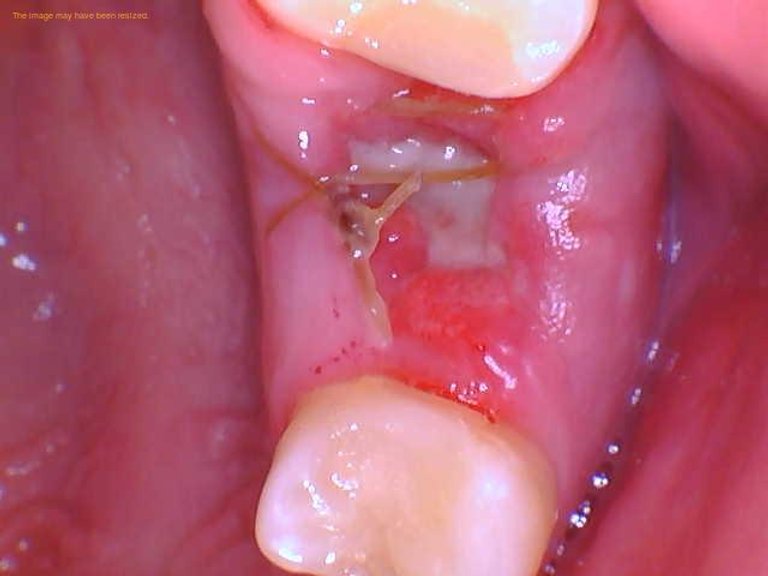

Types of Wisdom Teeth Stitches

Wisdom teeth stitches can be classified into two main categories: dissolvable stitches and non-dissolvable stitches. Dissolvable stitches, as the name suggests, are designed to dissolve on their own over time, typically within a week or two. Non-dissolvable stitches need to be removed by the dentist after a certain period, usually around one to two weeks post-surgery.

Colors of Wisdom Teeth Stitches

The color of wisdom teeth stitches can vary depending on the type of material used and the stage of the healing process.

White Stitches

White stitches are commonly used in dental procedures. They are often made of materials like nylon or silk. White stitches are more discreet and blend in with the natural color of the gums, making them less noticeable.